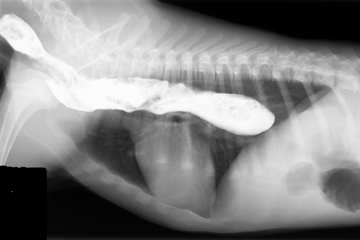

For an esophagram, the patient is given a barium paste or liquid suspension to evaluate esophageal motility, mucosal irregularites and size.